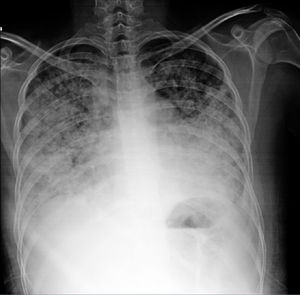

Se ha descrito asociación a títulos elevados de anticuerpos anti-dsDNA. La utilidad del lavado broncoalveolar (LBAV) reside en descartar infección, característicamente se observa celularidad incrementada a expensas de polimorfonucleares activados3. La toma de biopsia puede limitarse a casos con dudas diagnósticas para exclusión de etiologías alternativas. Los hallazgos son inespecíficos: daños a pared alveolar y necrosis, infiltración por células inflamatorias, edema, hemorragia y membranas hialinas16. Algunos expertos cuestionan la existencia de este síndrome a menos que se demuestre alguno de los siguientes: fibrosis intersticial, vasculitis, cuerpos de hematoxilina, neumonitis intersticial, alveolitis o pleuritis27. Resulta de utilidad recordar que, con fines de diagnóstico, el establecimiento de neumonitis lúpica es casi siempre simultáneo con exacerbación de la enfermedad en general con afección multiorgánica (p.ej., afección renal y serositis) y ocurre en la mayoría de casos en presencia de anticuerpos anti-SSA (82%). Por lo tanto, la combinación de neumonitis con afección multiorgánica y positividad para anti-SSA apoyan el diagnóstico29. En la figura 2 se muestra un ejemplo tomográfico de paciente con neumonitis lúpica.

Mujer de 24 años con LEG de 4 años de evolución caracterizado por manifestaciones predominantemente musculoesqueléticas y hematológicas (anemia hemolítica autoinmune). Ingresada al servicio de urgencias por cuadro de 10 días de evolución consistente en disnea, tos seca y posterior expectoración hemoptoica en 6 ocasiones. A su ingreso se encontraba taquicárdica e hipoxémica. En la tomografía destacó vidrio despulido de predominio bibasal. Tras descartar proceso infeccioso se consideró posibilidad de neumonitis lúpica. Recibió pulsos de metilprednisolona y ciclofosfamida con mejoría.